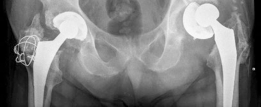

For anyone wondering about Acetabular Revision: Solving Challenges Post Two-Stage Arthroplasty, A **title acetabular revision** is a complex procedure addressing issues like septic loosening, dislocation, and significant osteolysis in total hip arthroplasty. For a 71-year-old male with a dislocated left THA due to infection and periacetabular bone loss, treatment involved a two-stage exchange followed by revision with a press-fit hemispherical cup and screw fixation.

Standard anteroposterior pelvis and cross-table lateral radiographs are mandatory. Judet views (iliac and obturator obliques) are critical for assessing the integrity of the anterior and posterior columns. However, plain radiography often underestimates the extent of osteolysis and bone loss.

These defects can typically be managed with a hemispherical, highly porous metal (tantalum or titanium foam) multi-hole acetabular component. The porous metal provides a high coefficient of friction for initial scratch fit and an optimal scaffold for biologic ingrowth. Particulate allograft may be used to fill contained cavitary defects prior to cup insertion. Multiple screws are placed into the safe zones of the ilium and ischium to maximize initial stability.